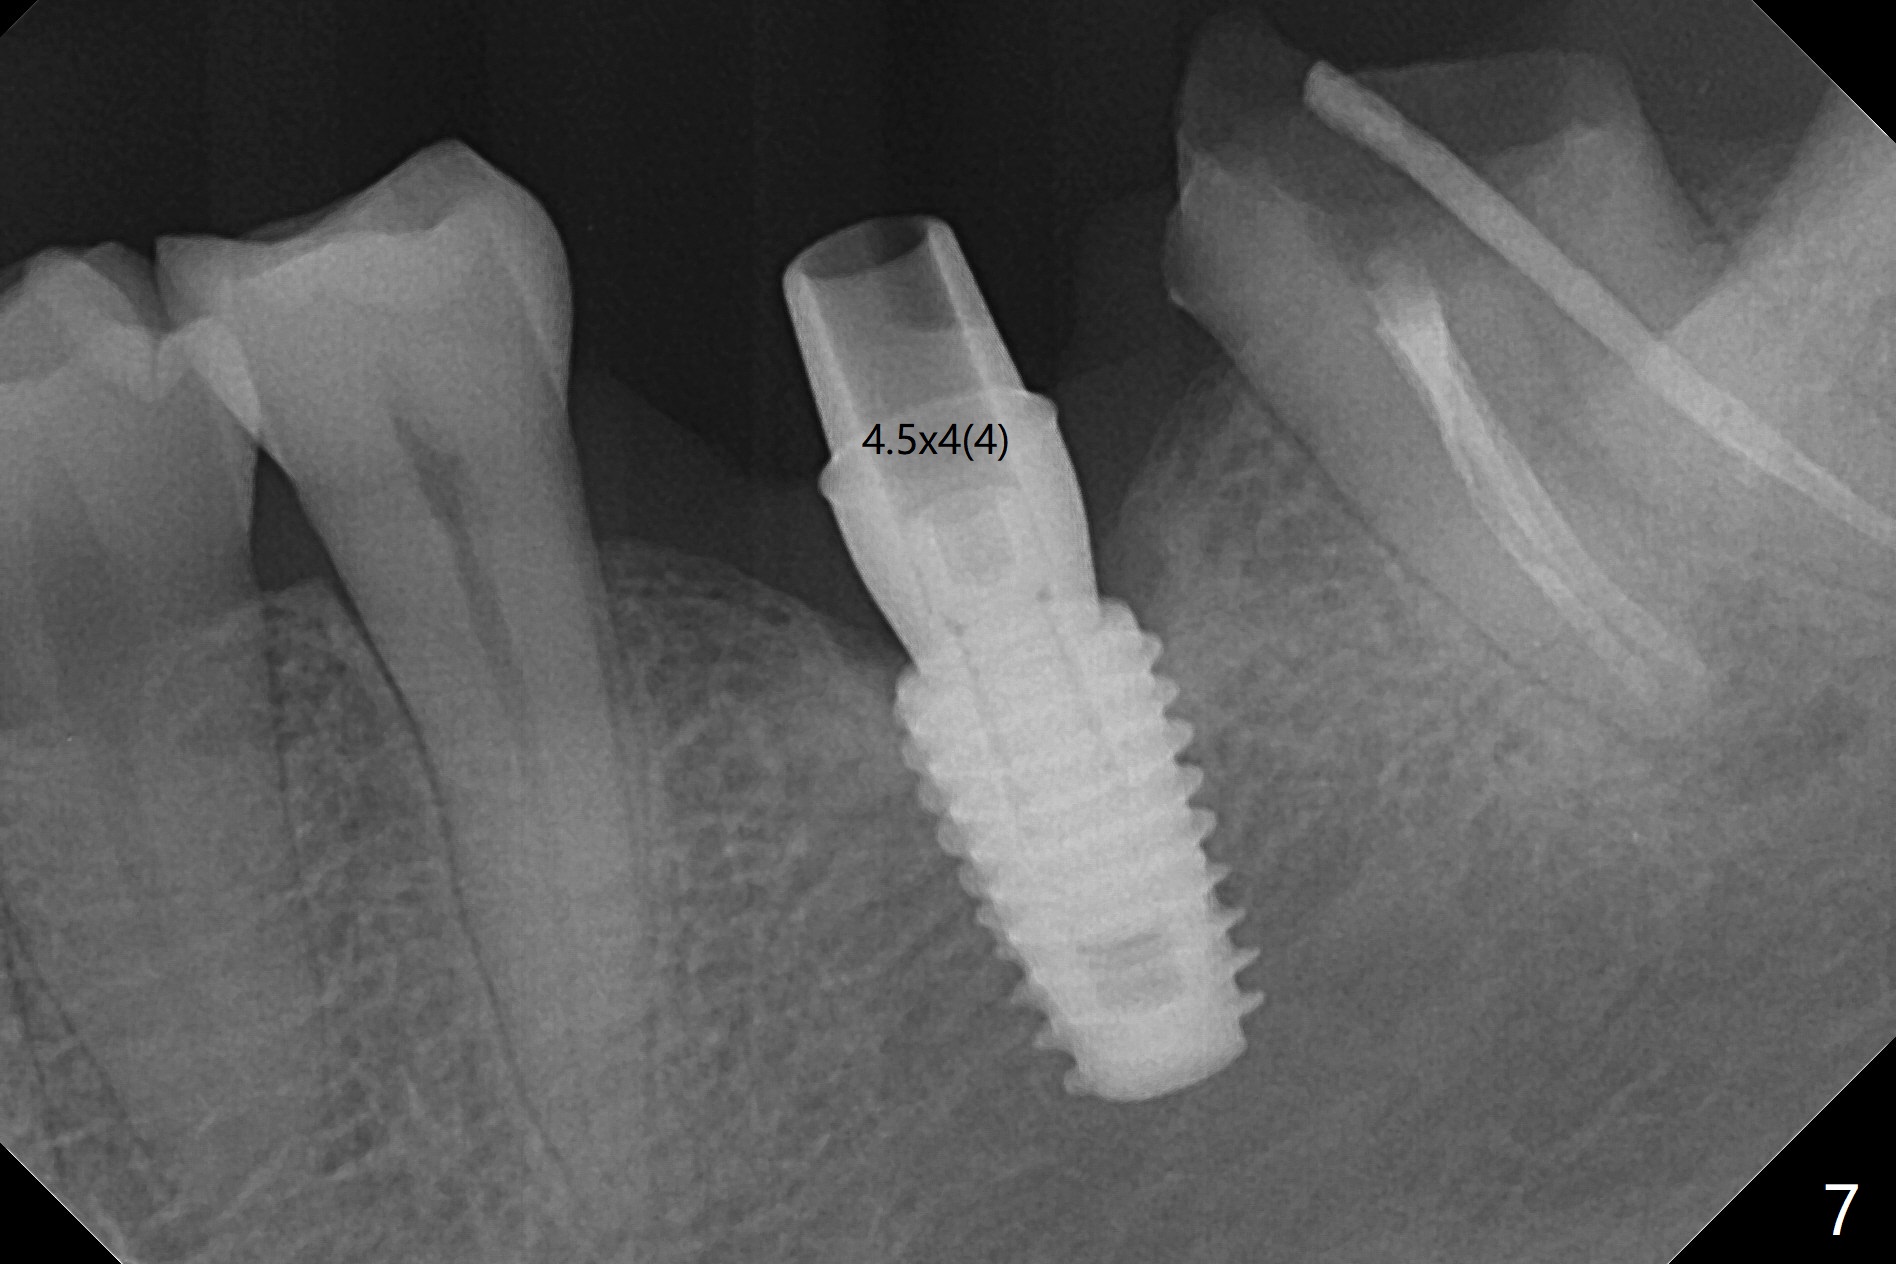

With one carpule of Xylocaine (34 mg with 17 mcg of Epinephrine), a 5x8.5 mm implant is placed at #19 in a timely and painless manner. The patient is pleased as compared to her previous implant placement at #3 and 30. Due to the thin buccal bone, the implant is placed ~.5 mm deeper than designed; a 6.5x4(2) mm healing abutment is incompletely seated (Fig.1). A smaller and skinny one (5.5x7(4) mm) is seated normally (Fig.2). Regional panoramic X-ray shows clearance from the Inferior Alveolar Canal (Fig.3 *). Although there is crestal bone resorption 6 months postop, the bone density next to the 1st thread is high (Fig.4 >). A 5.5x4(4) mm cemented abutment is placed for impression. The patient returns with #18 crown dislodgement and #19 crown loosening 11 months post cementation (Fig.5 <: gap between implant and abutment). Since the crown and abutment are unable to be torqued properly, they are removed (Fig.6). A narrower abutment is able to be seated apparently completely while a metal post (Fig.7 *) is tried in in the distal root of #18. To reduce the chance of re-fracture of #18 crown, the tooth #15 needs to be distalized orthodontically so that an implant will be placed at #14 (Fig.5).